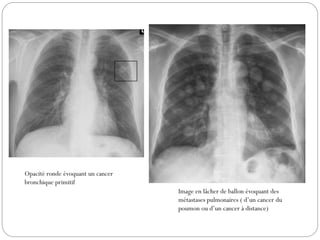

Opacité ronde évoquant un cancer

bronchique primitif

Image en lâcher de ballon évoquant des

métastases pulmonaires ( d’un cancer du

poumon ou d’un cancer à distance)